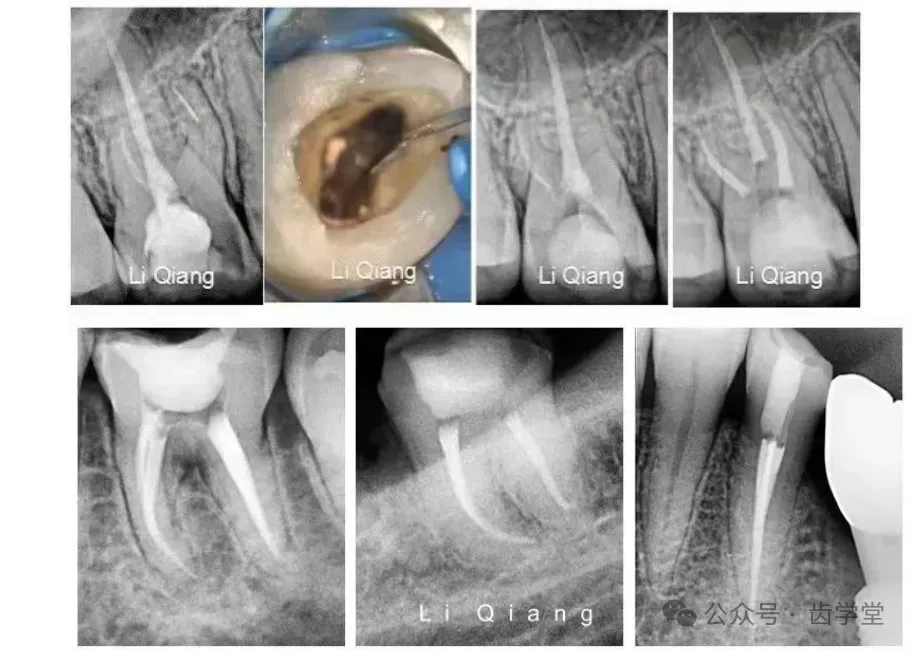

3. 生物陶瓷冷牙胶单尖充填技术的规范操作:详解生物陶瓷根充材料(如iRoot SP)的特性与单尖法优势,结合病例演示操作流程与质量控制要点。

4. 热牙胶垂直加压充填术与连续波技术:对比两种热牙胶技术的适用场景(如弯曲根管、扁形根管),解析加热温度、加压力度的控制技巧,提升根尖封闭效果。

4.根管中上段器械分离取出术(显微示教,不实操):导师通过显微镜演示器械分离取出,解析器械分离的应急处理逻辑。